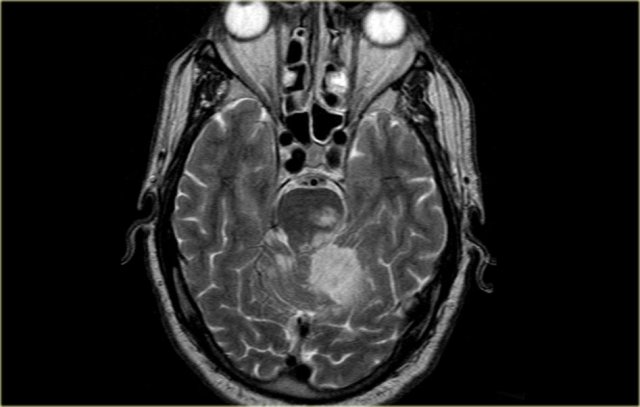

On the left MR-images of a left-sided PICA-infarction.

In unilateral infarcts there is always a sharp delineation in the midline because the superior vermian branches do not cross the midline, but have a sagittal course.

This sharp delineation may not be evident until the late phase of infarction.

In the early phase, edema may cross the midline and create diagnostic difficulties.